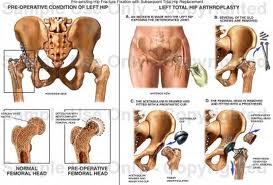

شکستگی لگن یک شکستگی جدی در افراد مسن می باشد. بیشتر شکستگی های لگن در افراد بزرگ تر از ۶۵ سال رخ می دهد و خطرات آن بعد از سن ۸۰ سالگی بیشتر می گردد.

علل شکستگی لگن

تصادفات رانندگی

افتادن از بلندی

در افرد دارای استخوان های ضعیف، شکستگی لگن در اثر ایستادن بر روی یک پا و یا چرخیدن پا رخ می دهد.